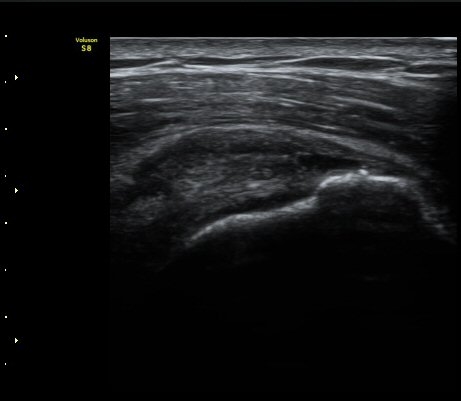

ÃÊÀ½ÆÄ °Ë»ç

À̵ιڱ٠Ⱦ´Ü¸é°Ë»ç¿¡¼­ Á¤¸Æ³¶ÀÇ ºÎÁ¾ÀÌ °üÂûµÊ(±×¸² 1).